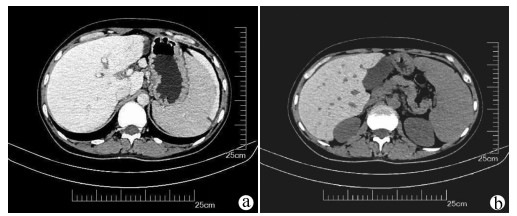

A case of splenic arteriovenous fistula with abdominal pain and gastrointestinal bleeding as the first symptoms

Yuanyuan CAI, Zhongwen WU, Juan LU

2021, 37(5): 1186-1188. DOI: 10.3969/j.issn.1001-5256.2021.05.043

Abstract(1011) HTML (291) PDF (2876KB)(49)

Abstract: